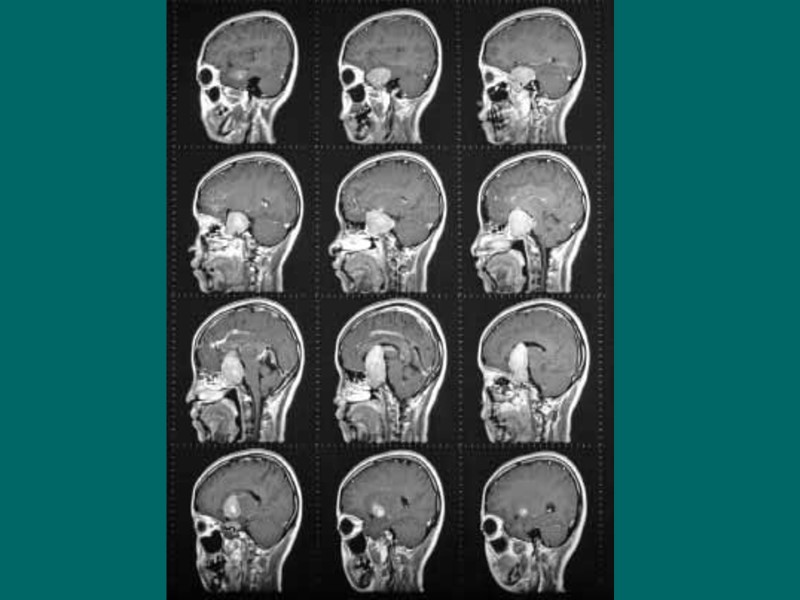

Гипоталамо-гипофизарно нейросекреторный комплекс – высший нейроэндокринный трансмиттер организма, координирующий эндокринную регуляцию метаболизма с работой ВНС и интегральными эмоционально-поведенческими реакциями лимбической системы. Состоит из: - Гипоталамус; - Нейрогипофиз; - Аденогипофиз

Гипофиз – орган, обеспечивающий процессы метаболизма и репродукции организма. - Аденогипофиз; - Нейрогипофиз